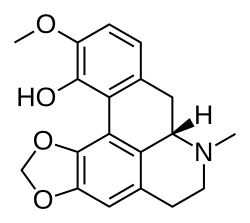

Many of the species in Corydalis contain alkaloids such as canadine and corydaline, which blocks calcium. The majority of these belong to the isoquinoline alkaloid group.[2] All parts of the plant are alkaloidal but the highest concentrations are present in the hollow root tuber.

Corydalis cava and some other tuberous species contain the alkaloid bulbocapnine, which is occasionally used in medicine but for which scientific evidence is lacking in regard to correct dosage and side effects.[3]